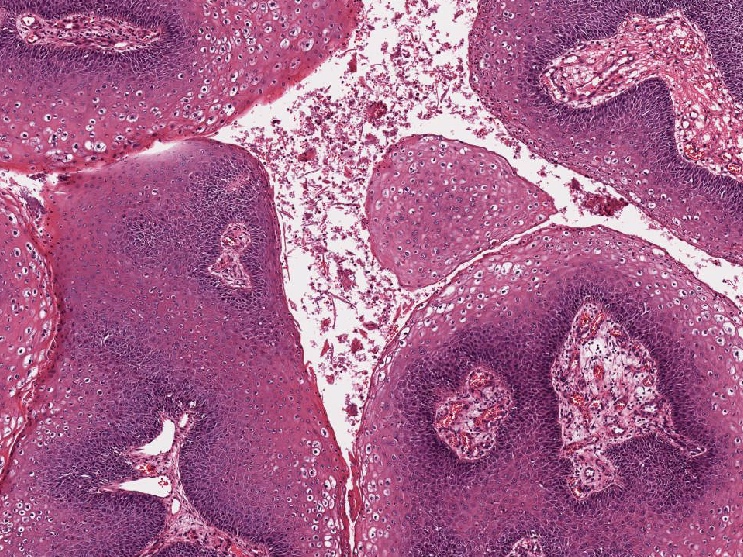

Microscopic (histologic) description

- Resembles condyloma acuminatum

- Diagnostic criteria

- Well formed papillae with a prominent central fibrovascular core

- Hyperkeratosis with parakeratosis and marked acanthosis

- Koilocytes on upper third of the squamous epithelium

- Chronic inflammatory infiltration

- Local extension and displacement of surrounding tissues but no evidence of dysplasia / invasion (WHO Classification of Tumours Editorial Board: Digestive System Tumours, 5th Edition, 2019)

- Low mitotic rate, usually confined to the basal layer with no abnormal mitoses (Histopathology 2017;70:938)

- About 30 - 35% may develop an invasive component; especially in high risk HPV positive cases (Virchows Arch 2020;476:543, Dis Colon Rectum 1989;32:481)

Microscopic (histologic) images